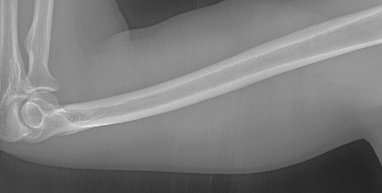

To tackle these problems, we propose to estimate the soft tissue image and bone image simultaneously without losing the linear relationship between image intensity and physical property of the imaging objects. Two examples from our method is shown in Fig. 1. The bone details are enhanced, which is theoretically guaranteed. The details of our method will be explained in later sections.

As shown in the left column of Fig. 1, bones are usually surrounded by the soft tissue. This physical configuration is similar with many natural scenes. One example is the foggy weather, as shown in Fig. 2 (a). The fog can be considered as “soft tissue” (low density) and the buildings can be considered as “bone” (high density).

Several results from our method are shown in Fig. 7. The left column is the original input image. The right two columns are the soft tissue and bone image, respectively. It can be told that the soft tissue image is smooth as we assumed. Meanwhile, the bone image has better image contrast as desired. Moreover, our method can reach real-time performance on these X-ray images. The running time of our method on these images is reported in Table I.